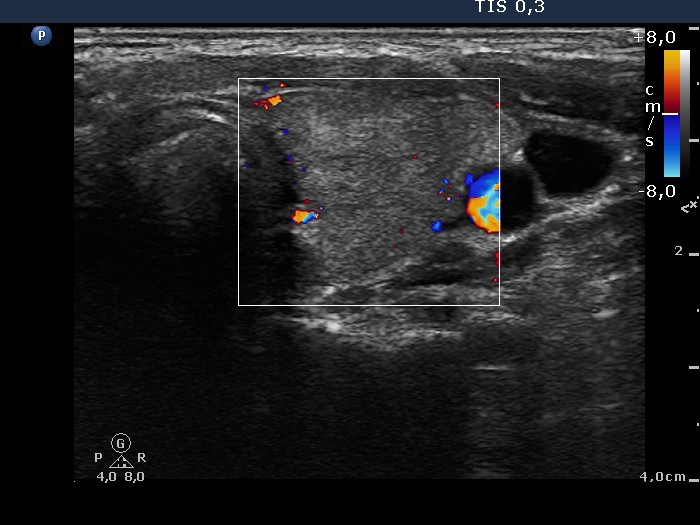

Follow-up investigation 36 months after first visit (ultrasonographic picture 6)

Patient on daily 10 mg methimazole therapy in euthyroid state

Left lobe, transverse scan, color Doppler mode. The vascularization is practically absent.